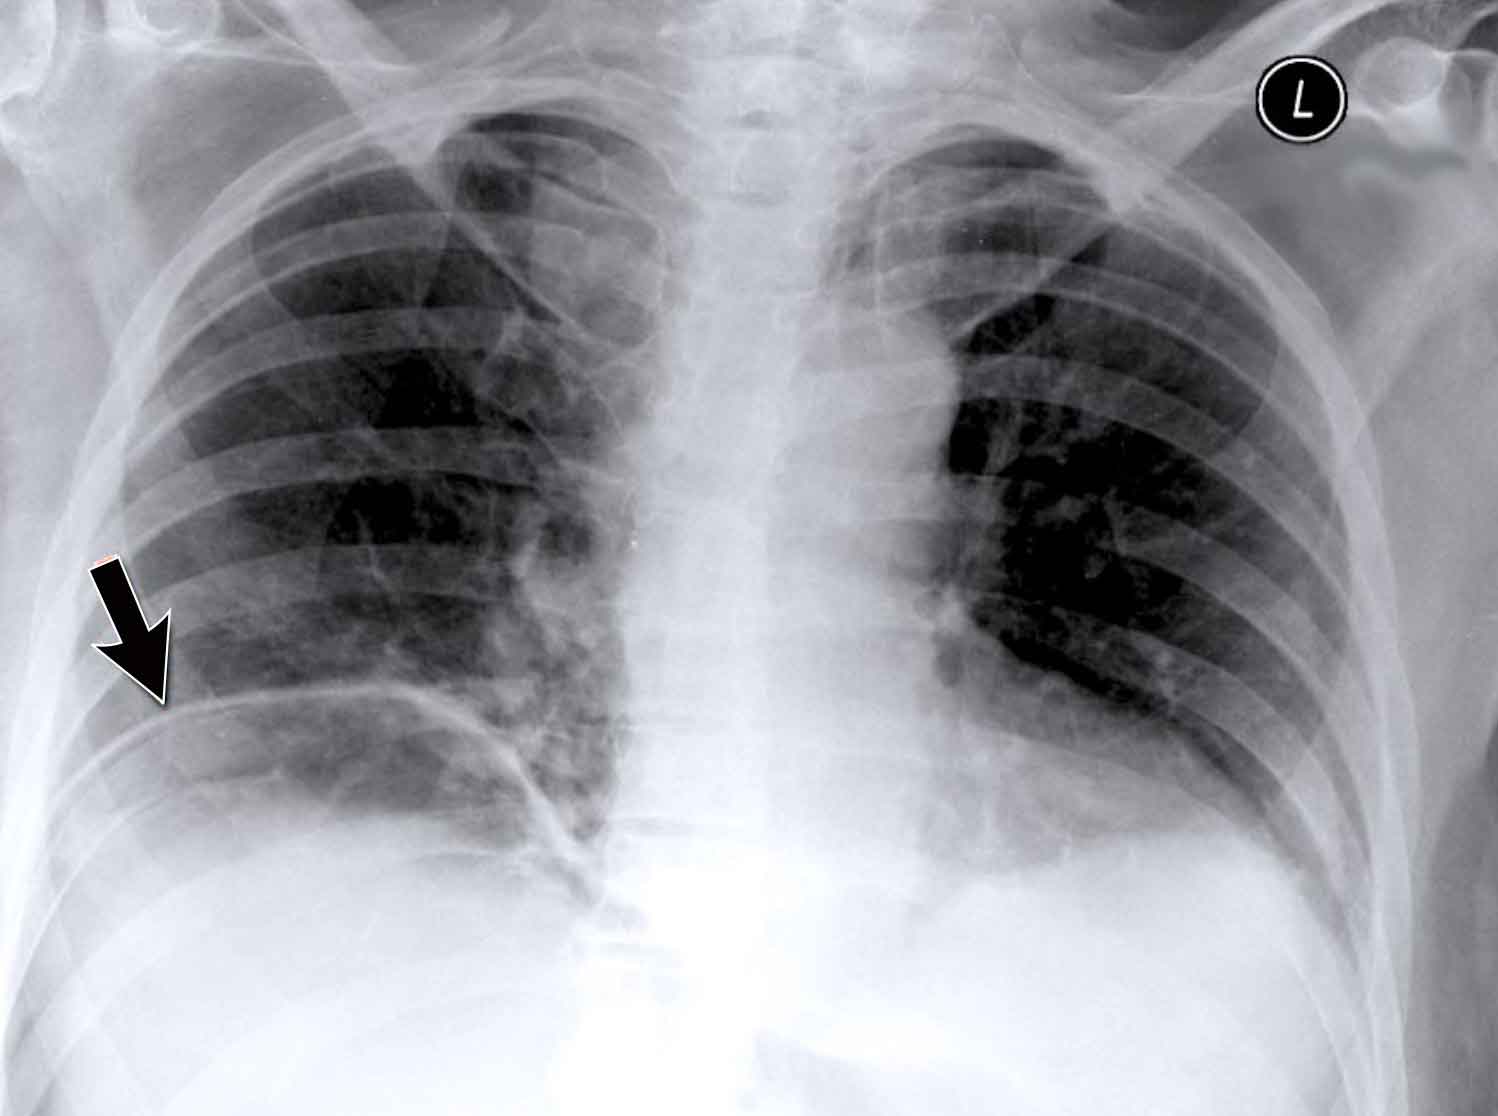

Hidden Areas (2): Right Lower Lobe Lesion

This example demonstrates a large mass in the right lower lobe that is challenging to identify on the PA view unless close attention is paid to the hidden areas.

- On initial inspection, the lesion is inconspicuous.

- However, with focused review of the subdiaphragmatic and retrocardiac regions, the abnormality becomes evident.

- Enlarge the image for better visualization.